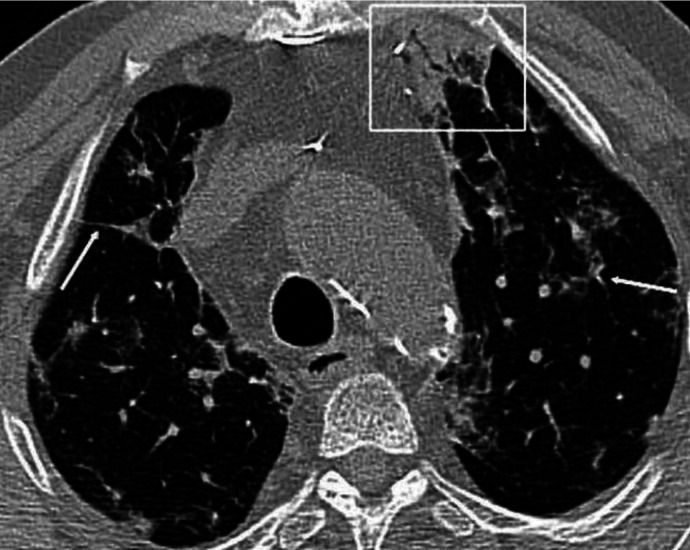

The aim was to compare the computed tomography (CT) semi-quantitative severity scoring (CT-SS) system assessments of COVID-19 pneumonia on initial and follow-up examinations according to the presence of comorbidities. Of the 278 real-time reverse transcription-polymerase chain reaction positive patients, 108 with a follow-up CT scan were evaluated. Then, all CT images were independently reviewed for CT-SS analysis by two reviewers. Reviewers were unaware of the patient laboratory and clinical findings. A quarter of patients had negative findings on their initial CTs. Sixty-one (56.4%) patients showed progression. Disease progression was more frequently observed in patients with type 2 diabetes mellitus (DM) and malignancies (p=0.044 and p=0.019, respectively). Follow-up CTs of patients with comorbidities, especially those with cardiovascular disease (56.4%) and type 2 DM (70.0%), demonstrated an increased frequency of diffuse involvement. The white lung sign was more frequently observed in patients with malignancies (60.0%). In this study, COVID-19 patients with comorbidity showed a higher rate of disease progression than those without comorbidity. Patients with comorbidities more frequently had severe CT findings with high CT-SS. These findings may serve as a guide in the COVID-19 pneumonia follow-up and treatment.